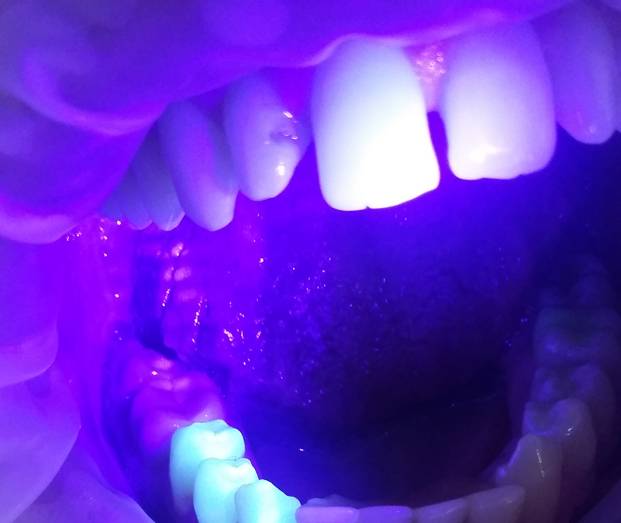

Эффективным методом распознавания начального кариеса является витальное окрашивание зубов, а также стоматоскопия с направлением на проблемные зубы пучка ультрафиолетового света.